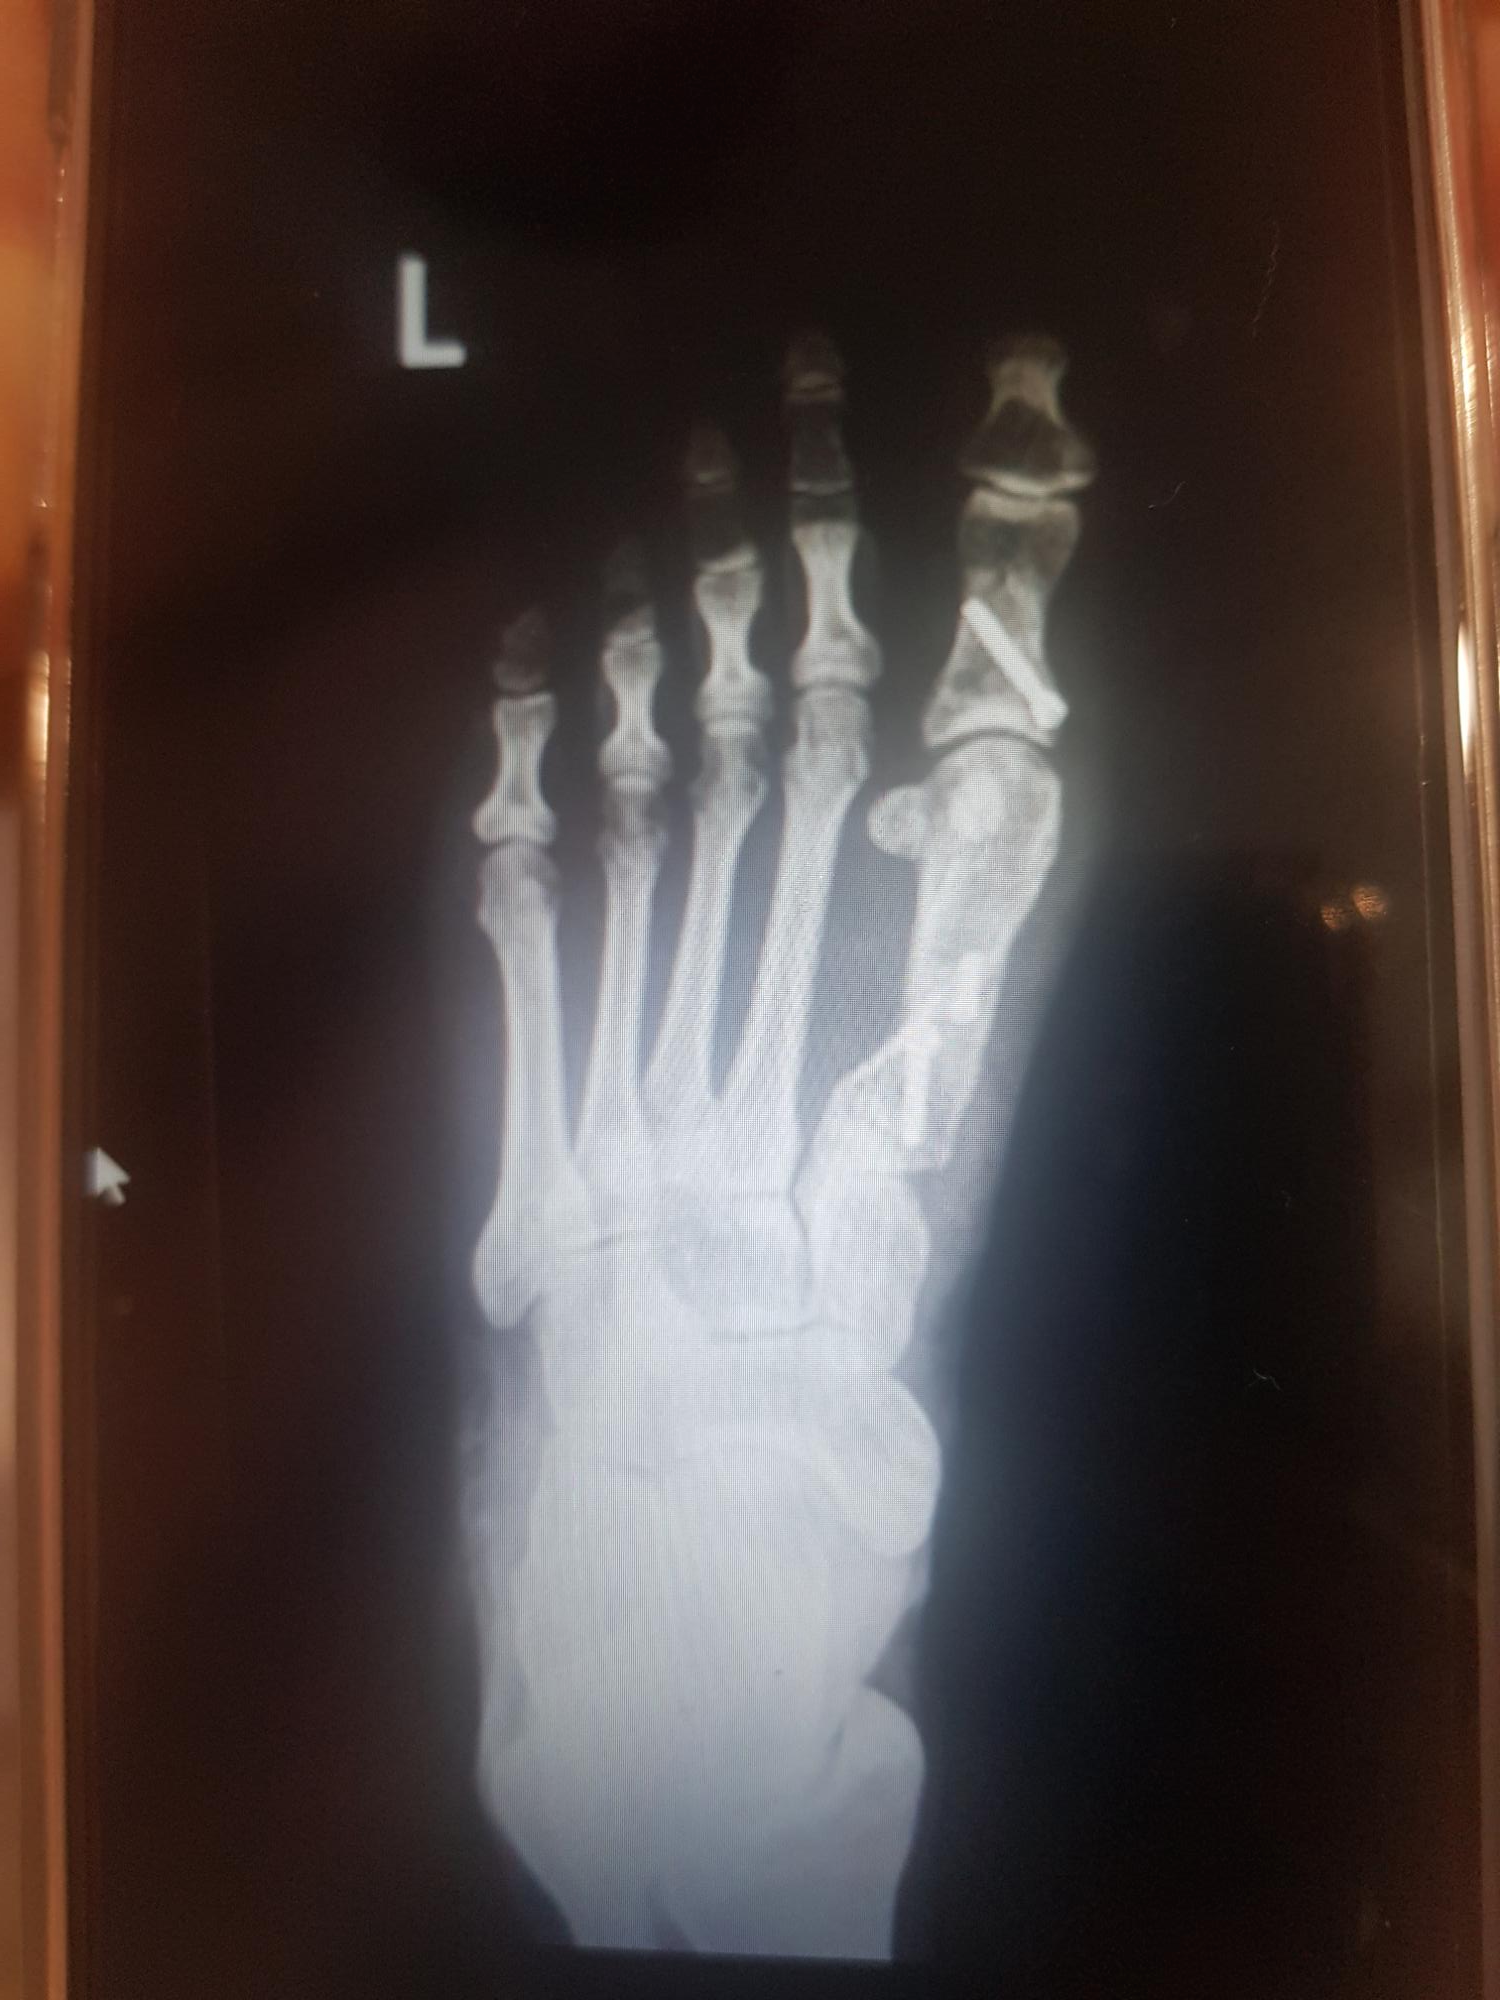

수술 전에 찍은 X-ray에요 :)

왼발은 핀제거 모습 오른발은 수술 직후 사진이에요.

자료를 공유가 어렵다 하시어 휴대폰사진을 찍었던 제인쨘 ㅋㅋ

( 혹 엑스레이를 얻게된다면 업데이트해놓겠습니다 )